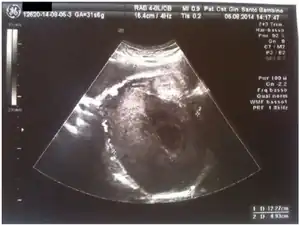

Pregnancy luteoma: ultrasound -

Diagnosis is by medical imaging: ultrasound, MRI.[1]

No treatments for luteomas are currently available. The luteomas can be detected through ultrasound if masculinization is apparent in the mother.[9] The fetus can be tested for gene type and if the fetus is female and the umbilical cord tests high for testosterone levels then the risks of masculinization of the fetus can be considered. Interventions cannot be made to change the outcomes, but the potential risks can be analyzed in order to make preparations. After the fetus is delivered the luteoma regresses on its own and only monitoring of the mother is needed after delivery. Depending on the sex of the fetus, exposure time and duration, the parents may need to decide if they will raise the child as male or female. Surgery may be necessary depending on what sex the child is going to be raised.[4]